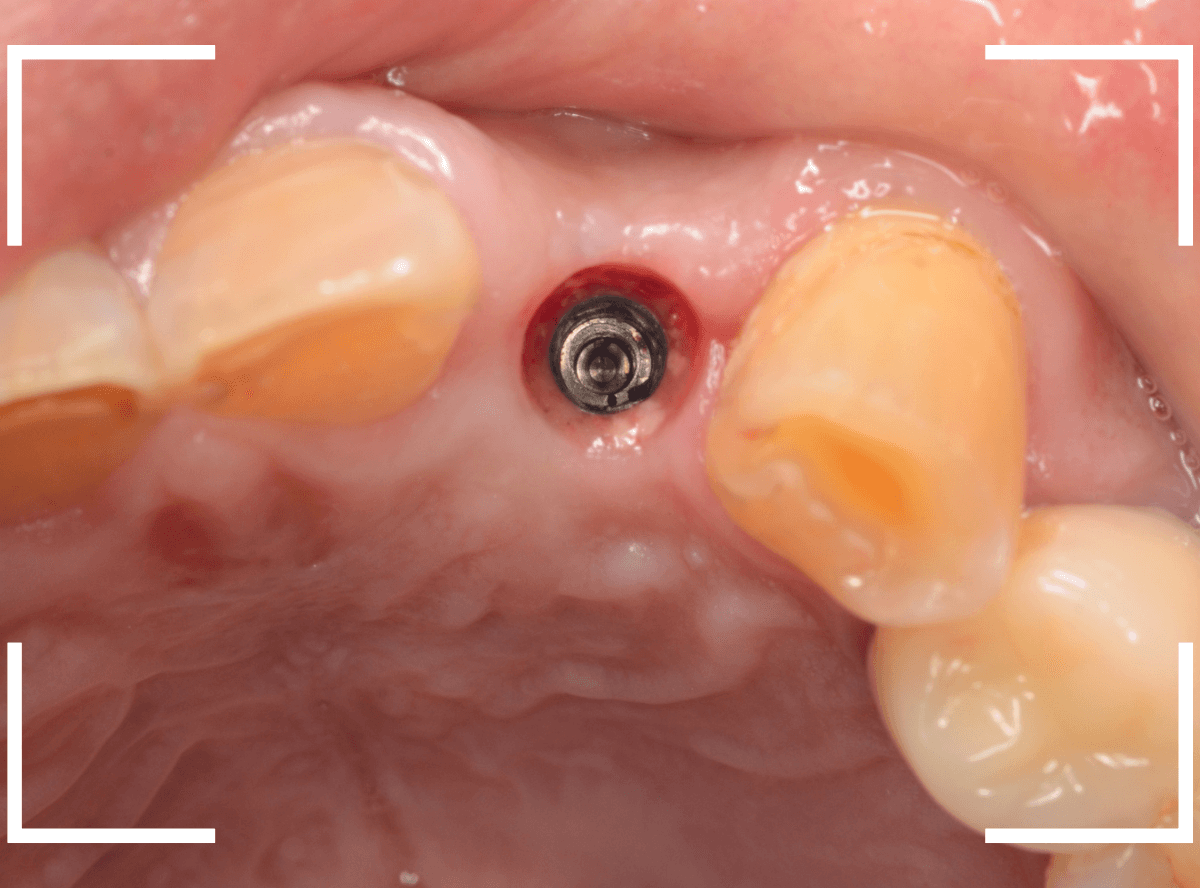

奥歯のインプラント治療例

下の奥歯にインプラントを埋入した方の例です。

インプラント周囲の歯肉も問題なく改善しています。

インプラントも問題なくsetできました。

よくたずねられるのですが、真ん中の穴はアクセスホールといい、インプラントの着脱の時に使用する、ネジ穴です。

set、調整が終われば、アクセスホールを埋めて、治療終了です。

何かあれば、アクセスホールを開けてインプラントを着脱できるようになっています。